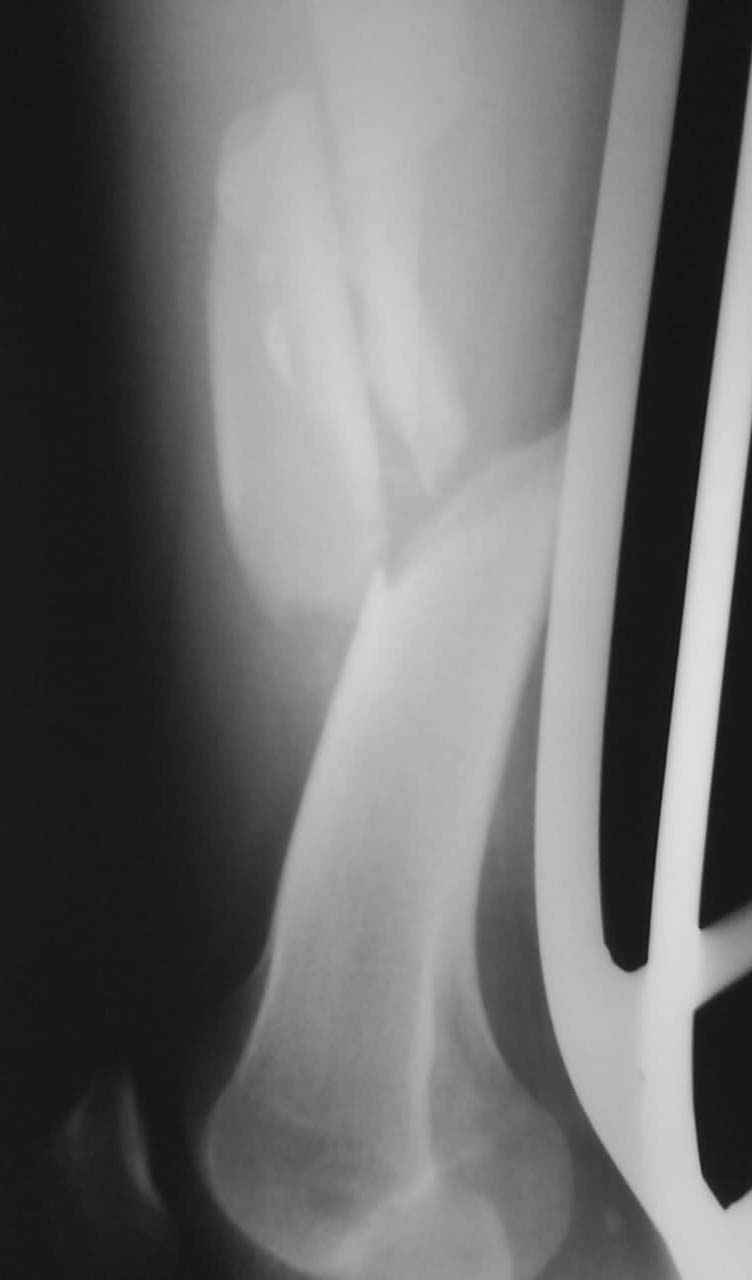

Привет из Нижнего Новгорода! К нам поступил пациент 25 лет с закрытыми переломами обеих бедренных костей, прошел месяц после травмы. Слева - внутрисуставной перелом, поэтому выбор здесь очевиден, открытая репозиция, стабильная фиксация, скорее всего LCP DF, а справа - мнения учёных, как говорится, разошлись. Лично я, как лечащий врач, за закрытый интрамедуллярный остеосинтез DFN. Со мной согласна половина коллектива, другая - за интрамедуллярный остеосинтез (DFN,UFN) но с открытой реопозицией, поскольку при закрытой методике все осколки останутся где-то сбоку, получится дефект и вдруг не срастется!Философский вопрос: что лучше - красивая рентгенограмма или сохранение кровоснабжения? Очень важно мнение коллег! Смирнов Алексей

Приветствую всех коллег!!Во первых слева хотелось бы видеть четкую боковую проекцию а лучше КТ. По р-мам есть сомнения насчет повреждения суставной поверхности. При подобных переломах даже внутрисуставных без смещения хорошие результаты показал закрытый ретроградный остеосинтез универсальным бедренным стержнем Деост.Кстати при внутрисуставном переломе возможно применение вместо винтов стягивающих болтов!!(См. метод.Деост).При переломе справа также стержень Деост. Однако без открытия Вам не удастся устранить интерпозицию, только промучаетесь!Из минимального разреза удалите интерпозициб и фиксируйте стержнем. Причем универсальный стежень Деост позволяет фиксировать дистально минимум на трех уровнях!